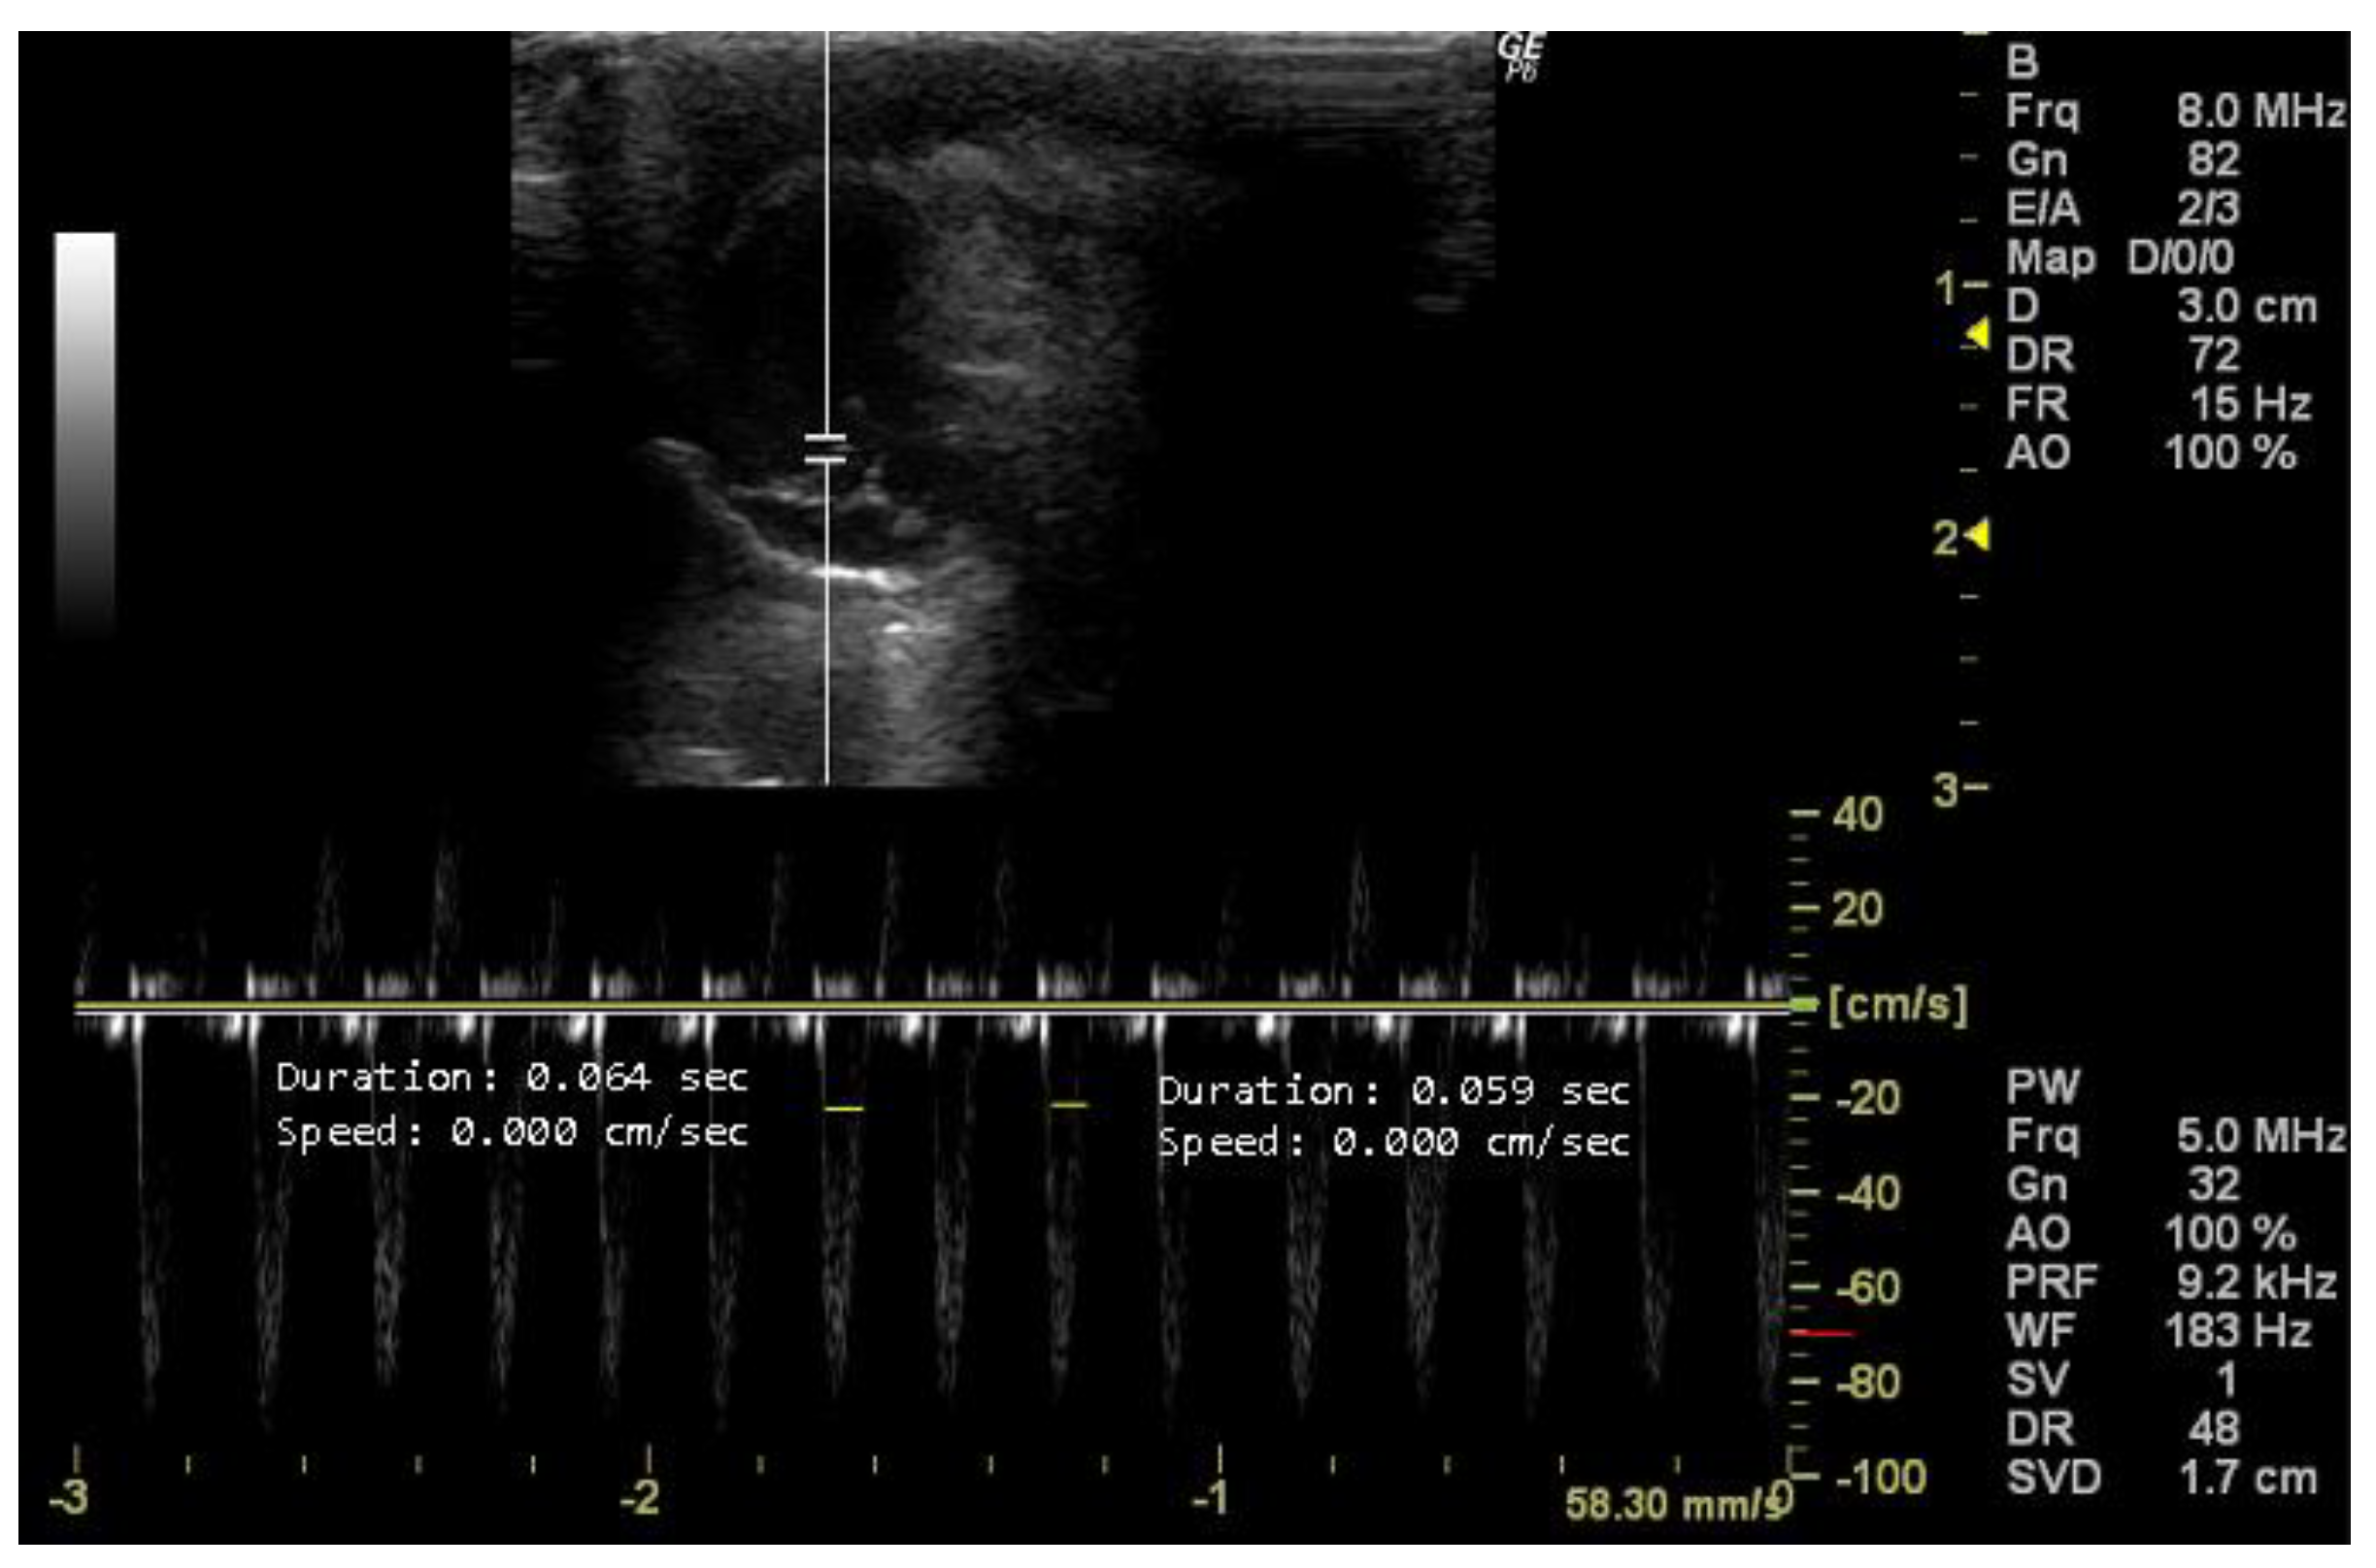

- How to measure HR

- How to measure E and A peaks